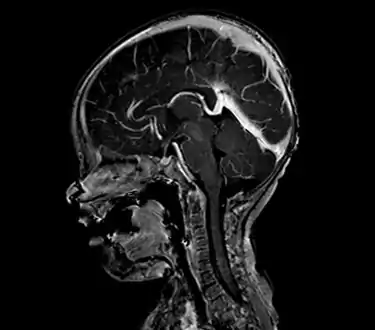

| Large arteriovenous malformation of the parietal lobe | |

A cerebral arteriovenous malformation (cerebral AVM, CAVM, cAVM) is an abnormal connection between the arteries and veins in the brain—specifically, an arteriovenous malformation in the cerebrum.[1]

An AVM diagnosis is established by neuroimaging studies after a complete neurological and physical examination.[5][11] Three main techniques are used to visualize the brain and search for AVM: computed tomography (CT), magnetic resonance imaging (MRI), and cerebral angiography.[11] A CT scan of the head is usually performed first when the subject is symptomatic. It can suggest the approximate site of the bleed.[3] MRI is more sensitive than CT in the diagnosis of AVMs and provides better information about the exact location of the malformation.[11] More detailed pictures of the tangle of blood vessels that compose an AVM can be obtained by using radioactive agents injected into the blood stream. If a CT is used in conjunctiangiogram, this is called a computerized tomography angiogram; while, if MRI is used it is called magnetic resonance angiogram.[3][11] The best images of an AVM are obtained through cerebral angiography. This procedure involves using a catheter, threaded through an artery up to the head, to deliver a contrast agent into the AVM. As the contrast agent flows through the AVM structure, a sequence of X-ray images are obtained.[11]